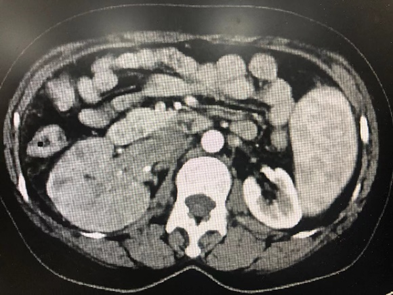

病例五,52岁女性,发现右肾肿物1月。CTU提示右肾癌7.7cm×6.8cm×11.6cm,伴MayoII级下腔静脉癌栓,长6.5cm。既往乙肝肝硬化。贫血。行机器人辅助腹腔镜右肾根治+下腔静脉瘤栓取出术,术者:张洪宪教授。术中发现肿瘤生长迅速,瘤栓较术前3天的影像学检查相比有进展,术中探查发现瘤栓已生长至下腔静脉肝后段,且质地极为糟脆,由于肝后下腔静脉不容易进行近心端阻断,遂采用不阻断近心端方法:充分游离肝后下腔静脉后,术中切开下腔静脉,采用“Milk”技术,用纱布沿下腔静脉近心端将下腔静脉瘤栓向下全部挤压出下腔静脉管腔,之后用纱布压迫下腔静脉近心端做临时阻断,同时缝合下腔静脉壁。